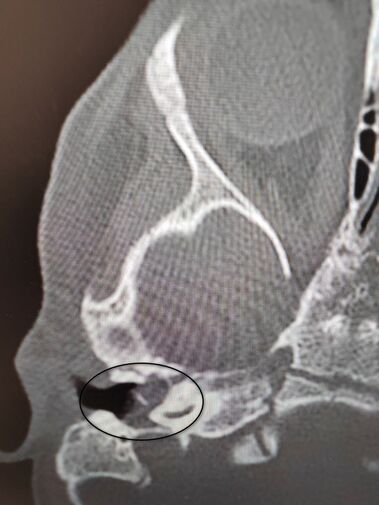

Девочка поступила в оториноларингологическое отделение больницы с хроническим гнойным средним отитом и подозрением на врожденную холестеатому барабанной полости — кистозное патологическое образование в среднем ухе. Врачи отметили, что подобное заболевание крайне редко диагностируется у детей в столь раннем возрасте.

«Холестеатома опасна тем, что может привести к рецидивирующему гноетечению и разрушению структур среднего уха, отвечающих за слух», — пояснили в пресс-службе ведомства.

После обследования и подтверждения диагноза пациентку направили на операцию, в ходе которой хирурги удалили у нее холестеатому, провели декомпрессию лицевого нерва и восстановили механизм звукопроведения.